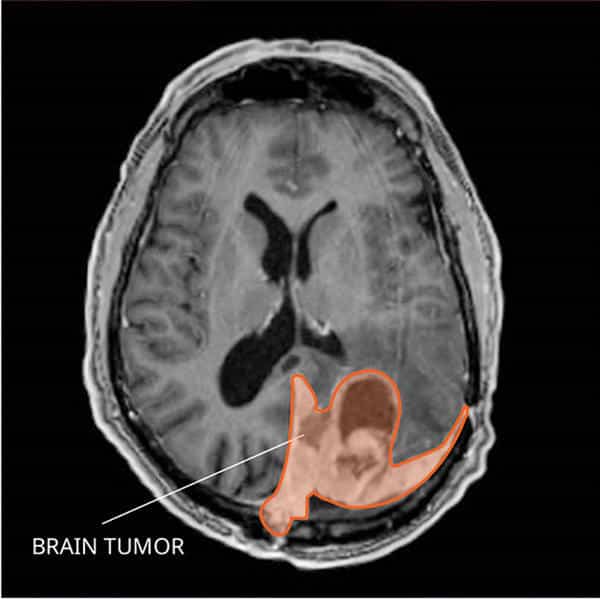

One of the key advancements in meningioma research lies in the development of diagnostic techniques. The diagnosis of meningioma usually involves a combination of imaging studies and histopathological examination. Non-invasive techniques like magnetic resonance imaging (MRI) and computed tomography (CT) scans have become invaluable tools in detecting and characterizing meningiomas. These imaging techniques allow healthcare professionals to visualize the tumor’s location, size, and surrounding structures, aiding in treatment planning.

Imaging Techniques

In addition to their diagnostic capabilities, imaging techniques have also advanced in terms of treatment monitoring and surveillance of meningiomas. With the development of functional imaging modalities like positron emission tomography (PET) scans, doctors can assess the metabolic activity of meningiomas, which can serve as a marker for tumor aggressiveness. Additionally, advanced imaging techniques, such as perfusion imaging and diffusion tensor imaging, provide valuable information about blood flow and tissue organization within and around the tumor, aiding in treatment planning and assessing treatment response.